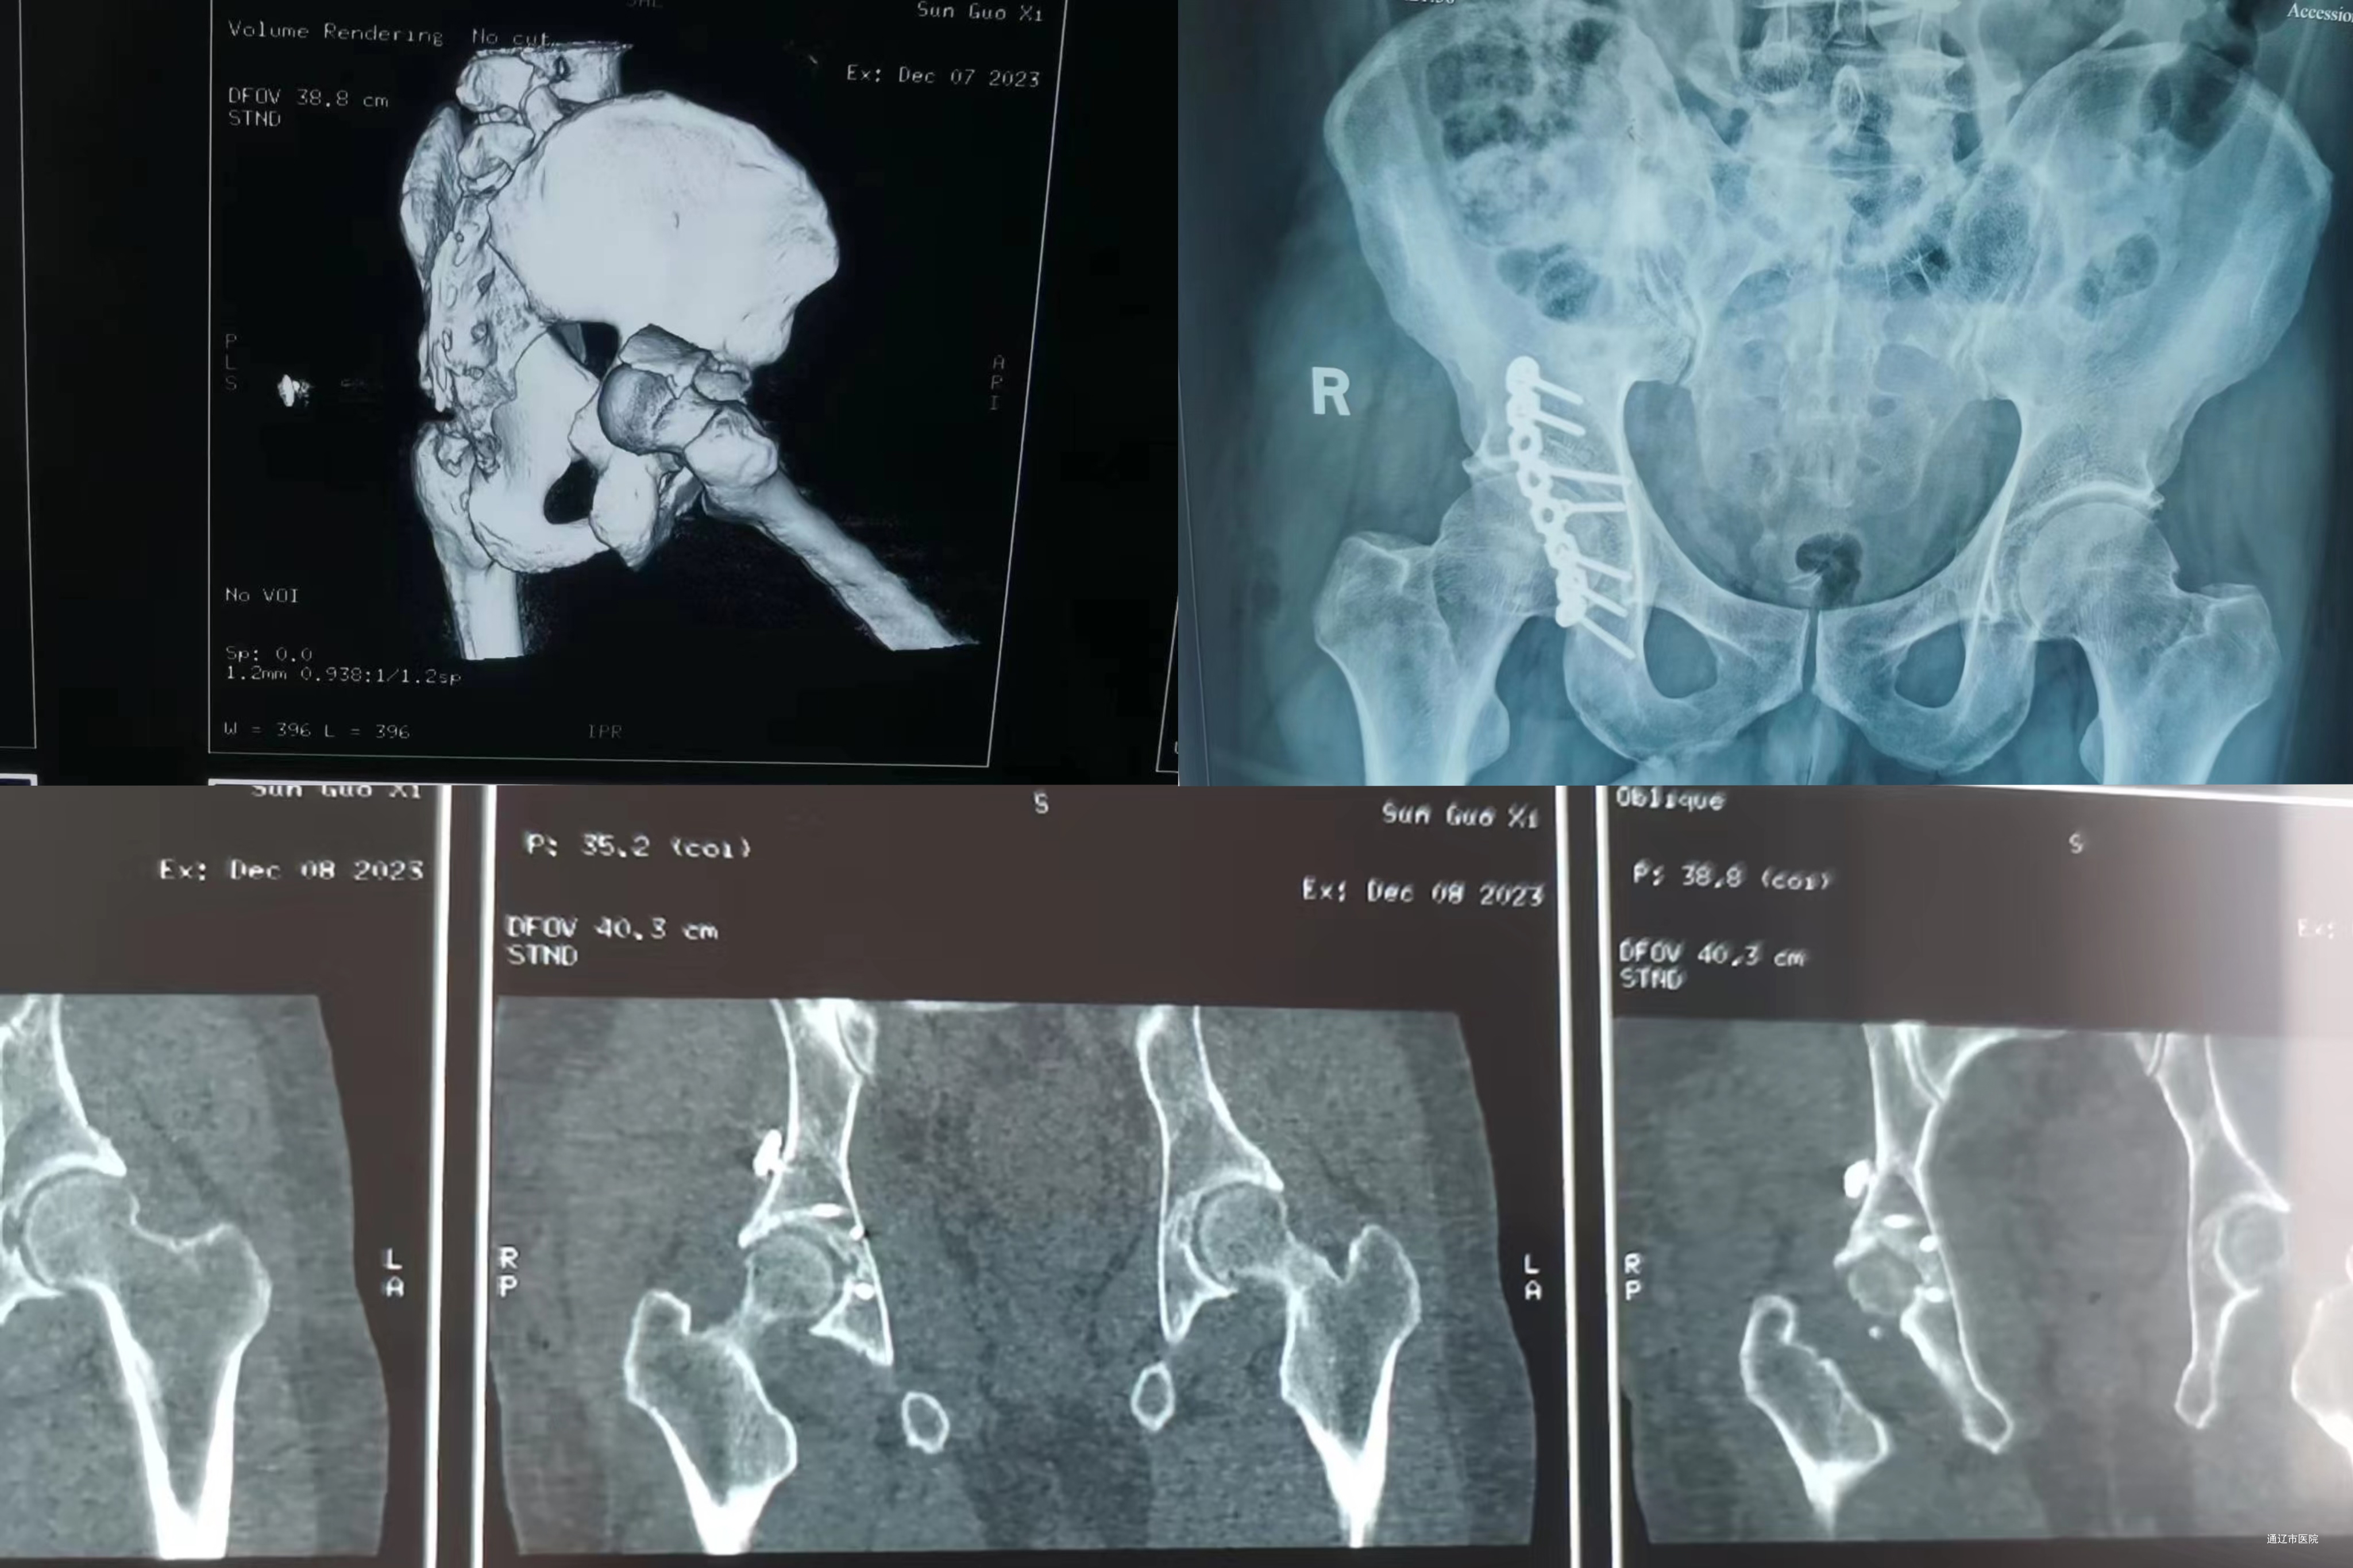

患者孙先生因车祸致右髋关节不能活动,右下肢麻木、内旋内翻畸形。前来库伦旗总医院骨科急诊就诊,经过兰忠煜副主任医师查看后,诊断右髋臼骨折、右髋关节脱位、坐骨神经损伤。需要急诊髋关节复位术,髋臼骨折内固定术。经过完善的术前准备,术中采用K-L入路,手术过程顺利。

术后患者恢复良好,同时也开创了库伦旗总医院髋臼骨折治疗的新篇章。